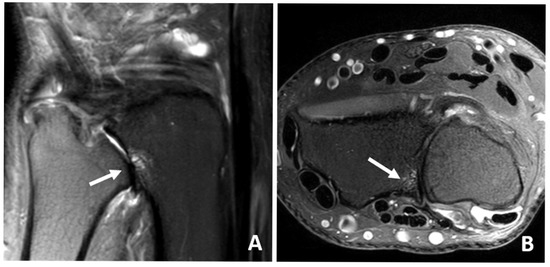

2.5. Magnet Resonance Imaging

3.4. MRI Scan